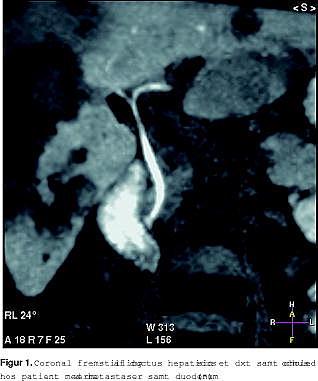

Ugeskrift for Læger havde den 13. juni 2005 et temanummer om galdesten. Det omhandlede også billeddiagnostik [1]. Til vor store forundring nævnes intet om en nyere MR-teknik. I dag laver man ikke kun MRCP (statisk billeddannelse ved hjælp af galdens vandindhold) men også funktionsbaseret fremstilling af galdevejene ved hjælp af enten kunstige stoffer eller paramagnetiske ernæringsstoffer (Figur 1 ).

I dag findes tre leverspecifikke kontraststoffer, som udskilles i galden. På Amtssygehuset i Herlev har vi i et stykke tid anvendt det nye kontraststof (CMC-001, CMC Contrast, Malmø, Sverige), der er baseret på ernæringsprodukter. Det skal ikke injiceres, men indtages peroralt, så oplysning om det enterohepatiske kredsløb fås også.

I modsætning til den beskrevne CT-teknik, som anvender de gamle ioderede galdekontraststoffer, der var kendt for høje bivirkningsfrekvenser, herunder allergilignende reaktioner, og langvarig ophobning af jod i thyroidea, så anvender MR-teknikken ingen røntgenstråling, og kontraststoffet er uden bivirkninger, hvorfor gentagne optagelser er mulige. Det er vores erfaring, at MR er langt at fortrække, idet man samtidig får fordelen af den gode bløddelsopløselighed. Det samme har været fremført i litteraturen [2-5]. Det kan være til patienter, hvor statisk MRCP ikke var sufficient, patienter med Klatskin-tumor, patienter med galdevejslæsioner samt forud for leverresektioner, hvor kortlægning af intrahepatiske galdeveje er ønskeligt.